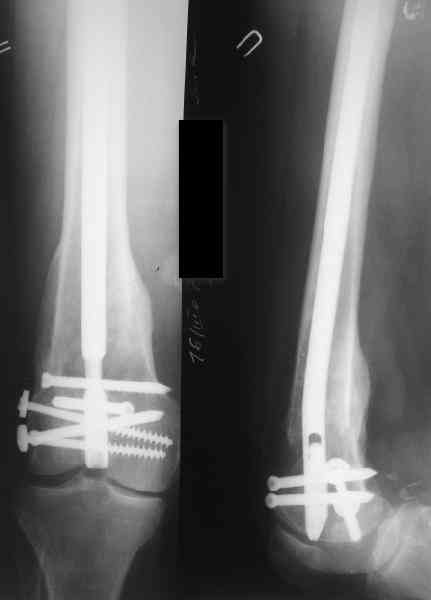

Пациенту М., 30-ти лет, 1,5 года назад в одной из московских больниц был выполнен остеосинтез бедренной кости штифтом UFN (диаметр штифта 9 мм).

К нам больной поступил с признаками ложного сустава бедренной кости, перелома

штифта и дистального блокирующего винта (images 1,2,3).

27 марта выполнено удаление блокирующих винтов (сломанный винт пришлось высверливать цапфен-бором), сломанного штифта (дистальный фрагмент удален через канал, образованный разверткой из коленного сустава - image 4),

рассверливание костно-мозгового канала, реостеосинтез штифтом UFN (при проведении штифта в дистальном отломке мы использовали поляризующий винт, диаметр штифта 10 мм). После операции в связи гемартрозом дважды (на 1 и 3 сутки) выполняли пункцию коленного сустава. Сейчас признаков скопления жидкости в полости сустава нет. Послеоперационные рентгенограммы - images 5, 6, 7.

Все здорово! Но, 1)- почему штифт 10мм, а не больше?, 2) - проксимальное блокирование одним вмнтом в статическом положении?

> Все здорово! Но, 1)- почему штифт 10мм, а не больше?, 2) - проксимальное

> блокирование одним вмнтом в статическом положении?

1) Мы располагали штифтом только данного диаметра.

2) По-поводу проксимлаьного блокирующего винта. Винт стоит на 3-5 мм выше нижнего

края динамического отверстия. Препятствий для компрессии отломков пока нет.